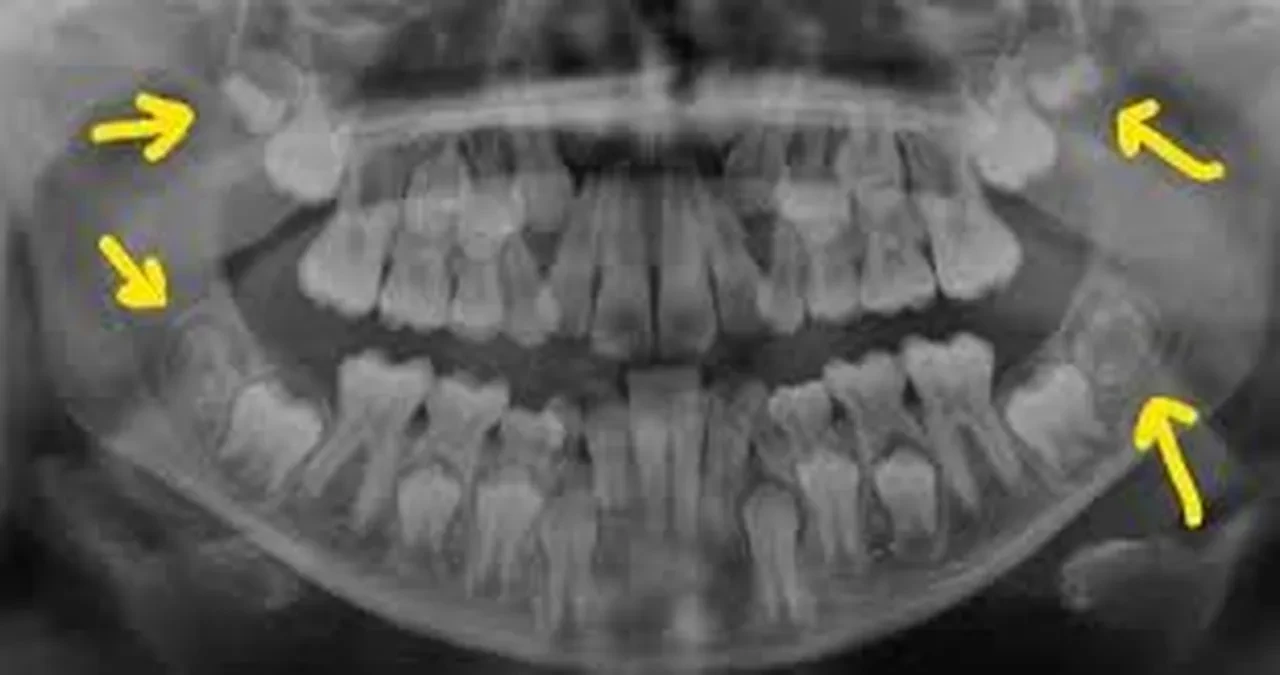

Uzun süredir yalnızca cerrahi operasyonla çekilip atılan yirmi yaş dişlerinin, aslında sağlık alanında büyük bir potansiyel taşıdığı anlaşıldı.

Ancak ABD ve Avrupa’da yüzde 80’i aşan oranlarda önleyici çekimlerle ortadan kaldırılan bu dişler, artık bir çöp değil, yüksek tıbbi değer taşıyan bir hazine olarak görülüyor.